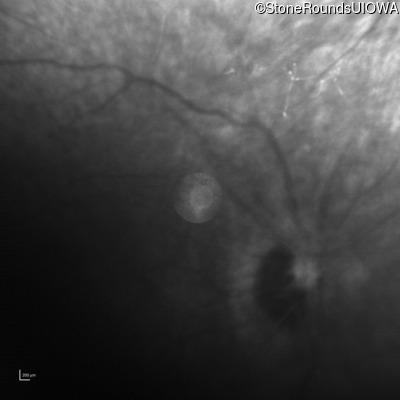

Infrared Fundus Photograph - Right - No Light Perception

Exemplar